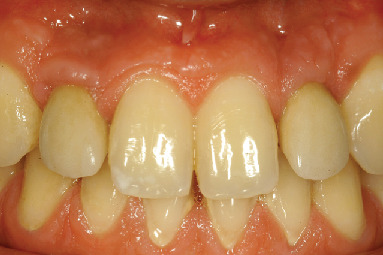

Clinical and radiological evaluations were conducted at 8 years (Figures 8 and 9) and 20 years from the prosthetic loading (Figures 10 and 11). After 20 years, the clinical examination showed healthy and stable soft tissues, with no signs of suppuration and bleeding on probing. Peri-implant probing was performed at six sites per implant, namely, mesiobuccal, buccal, distobuccal, mesiopalatal, palatal, and distopalatal. In all said sites, probing depth values ≤ 4 mm were observed. An adequate amount of attached keratinized tissue was present apically to the gingival margin. The quality and stability of the gingival architecture were supported by the radiographic analysis. The 8-year and 20-year orthopantomographs were scanned to obtain digital images with a resolution of 1200 dpi. The digital images were imported in a specialized computer software (ImageJ 1.49v, Research Services Branch, National Institutes of Health, Bethesda, MD, USA). The calibration of the pixel/millimeter ratio was performed on the basis of a known distance, namely, the length of the implants. The 8-year orthopantomograph revealed no detectable marginal bone resorption, calculated as the distance between the most apical bone-to-implant contact visible in the scanned image and the implant-abutment connection level at the mesial and distal aspects (Figure 9). The same measurements were performed in the 20-year orthopantomography (Figure 11); however, it was not possible to obtain reliable data due to metal artifacts. Nonetheless, the clinical findings suggested the presence of stable marginal bone levels circumferentially around the implants.

Figure 8.

Clinical situation at 8 years.

Figure 10.

Clinical situation at 20 years.